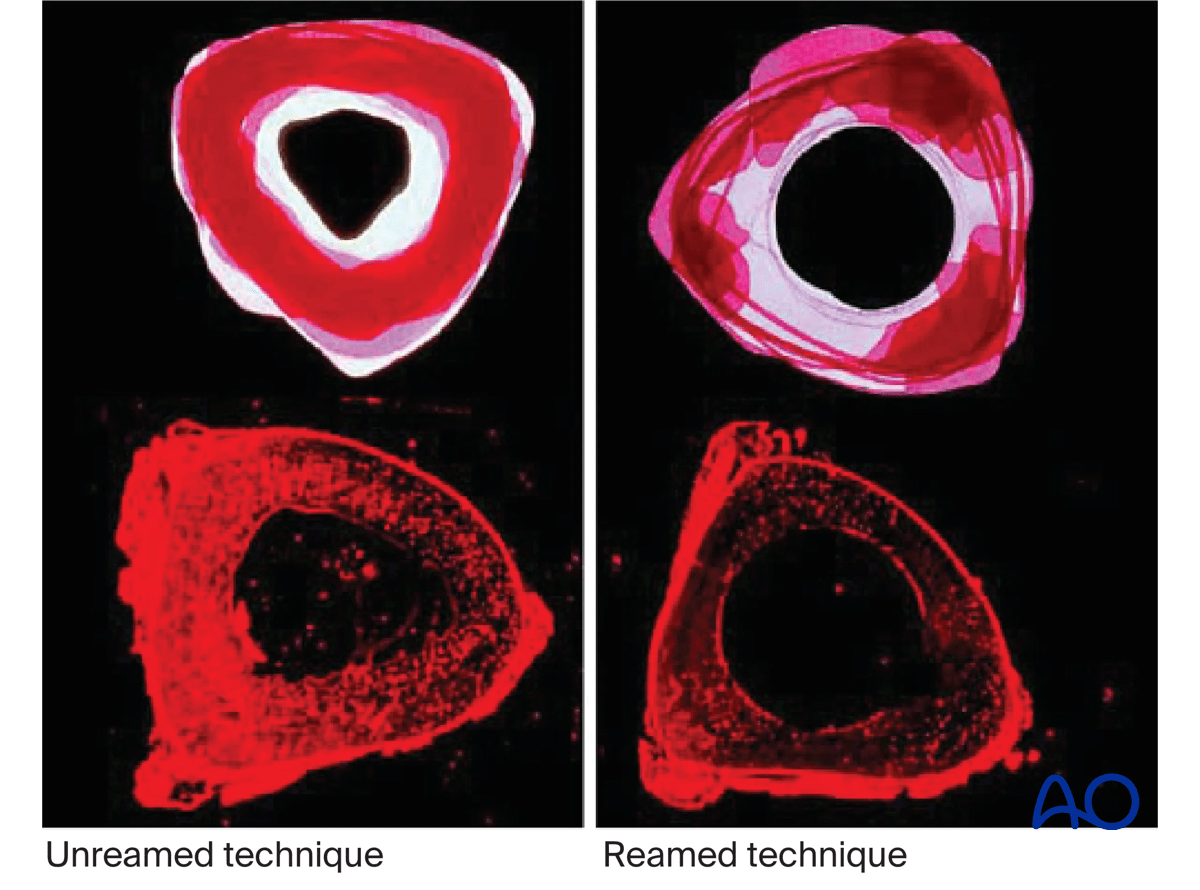

Reamed nailing

The diameter of the tibial medullary canal varies between 13 mm and 8 mm or less. Reamers can be used to enlarge the medullary canal for larger diameter nails. Such nails permit larger diameter locking screws. The strength and durability of screws and nails increases with their diameter. The medullary canal should be reamed so that it is slightly larger than the intended nail diameter (usually about 1.5 mm more), to ease nail insertion. Stability is increased with the reamed technique, because the nail fits snugly in a longer portion of the tibial shaft.

Reaming damages the medullary blood supply and causes temporary thermal necrosis of the diaphyseal bone. Theoretically, this increases the risk of infection, which may be relevant for open fractures. Clinical studies have not demonstrated this.

The surgeon should consider if the benefits of reaming are worth the associated risks, particularly in severe open fractures.

The individual patient’s medullary canal size, as well as probable mechanical stresses, must be included in this consideration.

Studies have shown increased union of tibial shaft fractures using reamed compared to unreamed intramedullary nails.